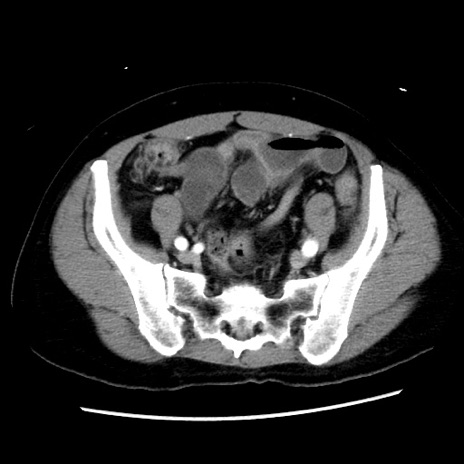

症例10(横断像)

【症例】 50歳代女性

【主訴】 腹痛

【現病歴】前日生レバーを食べた。今朝に排便あり。 昼前に突然発症の腹痛を生じ、当院救急外来を受診した。

【既往歴】 子宮筋腫にてで子宮全摘後

【身体所見】 意識清明、腹部:平坦、軟、下腹部やや左を中心に圧痛・反跳痛あり、筋性防御あり

【データ】WBC 7800、CRP 0.07